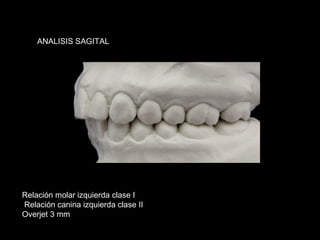

ANALISIS SAGITAL

Relación molar izquierda clase I

Relación canina izquierda clase II

Overjet 3 mm